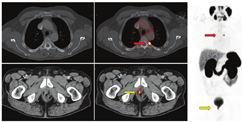

与PET/CT结合可能在许多方面影响放疗计划。首先,在PET/CT定义的目标体积内总体疾病可以给予更高剂量。图2显示了1例复发性前列腺癌患者的典型SRT计划,以及1例68Ga-PSMA阳性的左侧髂内淋巴结接受的剂量高于周围盆腔淋巴结患者的SRT计划。剂量显示为热图。剂量-体积直方图显示了涵盖每个描绘体积的给定百分比剂量。图中显示,68Ga-PSMA阳性淋巴结(加上边缘)100%接受超过65 Gy(图中虚线),而整个盆腔淋巴结体积100%接受45 Gy(图中紫色实线)。

第二,CTVs可以被扩展到包括目前一线影像学未见的疾病区域,并且通常不是一致的CTVs靶点(图3)。第三,转移性疾病的证据表明,单靠局部治疗是无法治愈的。在寡转移性疾病(较低的转移性疾病负荷,在3~5处部位出现不同表达)的背景下,许多医师提供转移导向治疗,旨在局部消融转移灶(图4,图5,图6),转移导向治疗是当前众多临床试验的主题[54]。最后,在某些PET/CT意外显示的弥漫性转移病灶的病例中,放疗可能是无效的。